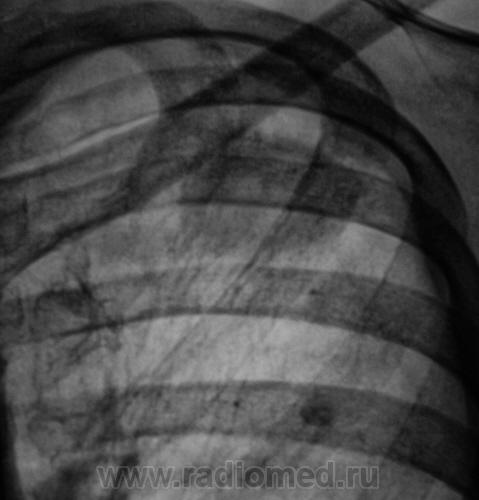

Выставляю томограммы.

11..Vystavlyayu..JPG12..Vystavlyayu.JPG13..Vystavlyayu..JPG

И еще.

14..Vystavlyayu.JPG15..Vystavlyayu.jpg16..Vystavlyayu.JPG17..Vystavlyayu.JPG18..Vystavlyayu..jpg

Итак, если, я правильно понял, то дифференциальную диагностику нужно проводить между периферическим раком легкого и туберкуломой?

Вообще-то дискуссия," что это периферический рак или туберкулома"- подтверждение старой истины:рентгенологически дифференцировать периферический рак и туберкулому практически невозможно.

Да, коллега, Вы совершенно правы. И даже наличие "архива", и даже наличие в окружающей легочной ткани отдельных очажков, не может на все 100 свидетельствовать, что это туберкулома, ибо известны случаи "поглощения", растущей опухолью "старых очагов". Наличие эксцентрического мелкофокусного единичного или множественного распада, также не может свидетельствовать только в пользу рака. Контуры неровные, нечеткие и даже с элементами полицикличности, и даже с мелкой лучистостью, достоверно не могут свидетельствовать ни о раке, ни о туберкуломе. Клиника, также не помощница в данном вопросе, также, как и зачастую специфические пробы. Касательно "дорожки", также вопрос спорный.

Мне, этот случай показался весьма интересным, ибо ни атипические клетки, ни МБТ выявлены не были. Завтра постараюсь выложить предыдущие снимки.

Пациент прооперирован в областном онкологическом диспансере. Окончательный диагноз, включая всевозможную морфологию - туберкулома.

"Местная" статистика, Субъекта Федерации ,свидетельствует, что в последнее время участились подобные случаи, когда при адекватном обследовании, после которого производилось оперативное вмешательство, при верифакации "опухоли", вместо желаемого "рака" оказывалась туберкулома. С одной стороны, конечно это хорошо, ибо саниция, есть санация, но с другой стороны, по всей видимости, свидетельствует и об определенных проколах...